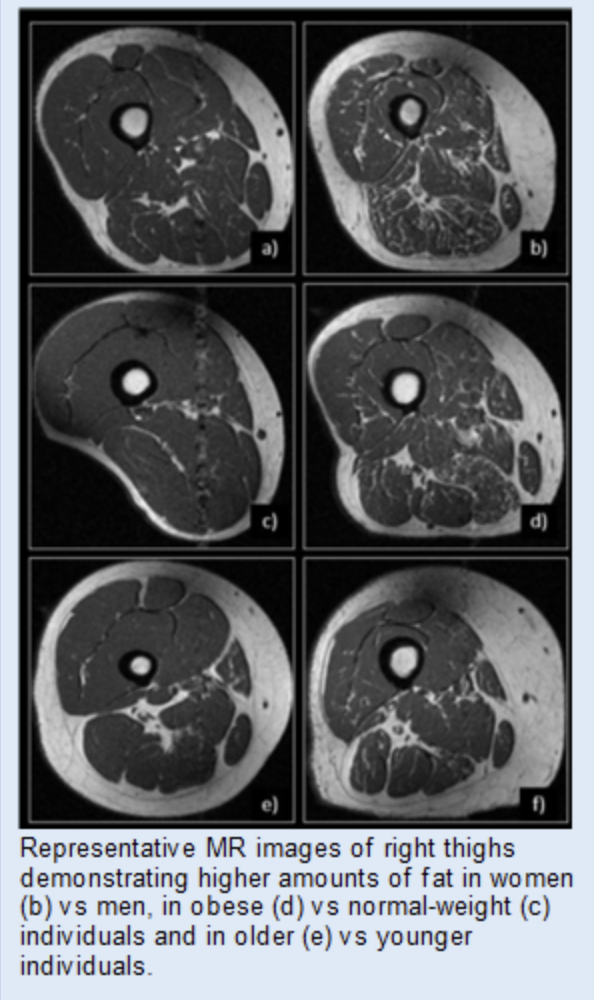

The Clinical and Translational MSK Imaging group (CTMI) uses standard and novel imaging techniques to study abnormalities of the musculoskeletal system. Our focus is on imaging biomarkers in osteoarthritis; the team has developed quantitative and semi-quantitative measurement tools to assess and monitor disease severity. These include Whole-Organ Magnetic Resonance Imaging Scores (WORMS) of the knee, composite scores to measure knee joint synovitis, and the Scoring Hip Osteoarthritis with MRI (SHOMRI) system to study the hip. In addition, artificial intelligence-based tools to measure muscle volume and fat infiltration, periarticular adipose tissue, and synovitis volume have been developed. Recently, we also investigated novel MR imaging techniques to reduce metal artifacts, low field MRI at 0.55T, and CT-like MR imaging techniques.